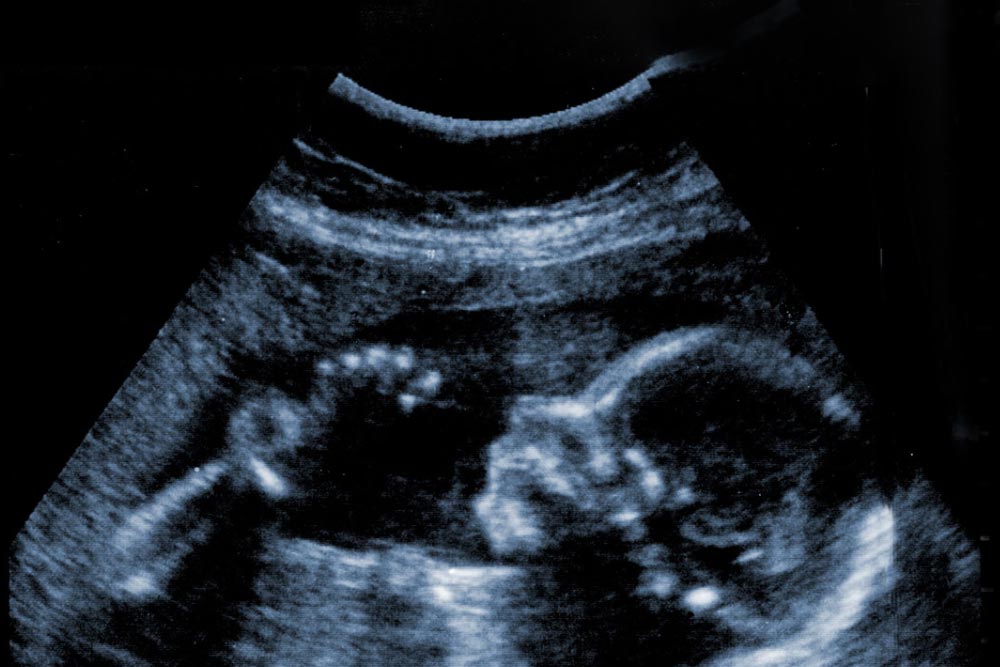

Get peace of mind with our comprehensive well-being baby scan at Basingstoke Numi Scan, included in all packages starting from 15 weeks and beyond. This traditional 2D scan focuses on tracking your baby's development, checking growth metrics, movement patterns, weight, placental position, amniotic fluid levels, and more. It's a crucial step after your initial NHS appointment.

Our well-being scan offers professional reassurance for expecting mothers who may have concerns about their pregnancy. It provides prompt peace of mind, offering an easier and faster alternative to NHS scans, which typically occur only at 12 and 20 weeks. With thorough checks for both you and your baby, it provides the necessary information to take action if needed, or simply offers reassurance and another chance to connect with your baby

All our scans are transabdominal, ensuring a non-invasive experience unlike transvaginal scans. Our handheld scanner gently glides over your abdomen with a lubricating gel, enabling our sonographer to capture high-quality ultrasound images without discomfort. To ensure optimal results, it's important to drink plenty of fluids before your appointment.